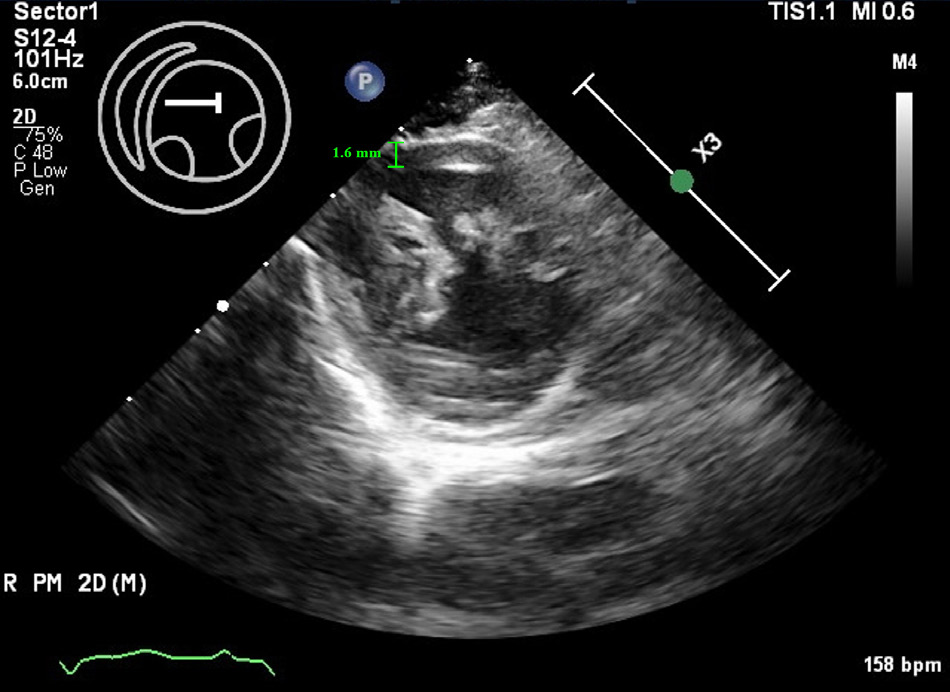

二维超声心动图显示在右胸骨旁长轴视图中,室间隔在舒张期出现局灶性增厚(最大直径11.01毫米 [3.00–5.20]),左心室后壁增厚(最大直径7.41毫米 [3.00–5.10]。在右胸骨旁短轴视图中观察到左心室游离壁局灶性变薄,厚度约为1.6毫米,并伴有低动力运动(下图)。

↑ B型超声心动图图像显示左心室游离壁局灶性变薄(绿色线)。

在右胸骨旁短轴视图中,前心尖壁厚度约为1.6毫米,并显示出低动力的心肌运动,符合薄壁及低动力心肌节段性心肌病的表现。在左心房中发现了自发性超声显影,表明血栓形成的风险增加(下图及视频)。

超声心动图检查发现室间隔和左心室后壁显著增厚,而心尖区域的左心室游离壁局部变薄至约1.6 mm,且心肌运动减弱,提示存在THyMS。此外,左心房收缩功能下降,左心房与主动脉比值增加,左心房内还出现了自发性超声显影,提示血栓形成风险增加。心电图显示左前分支阻滞,表现为左轴偏移,II、III和aVF导联出现小R波和深S波。